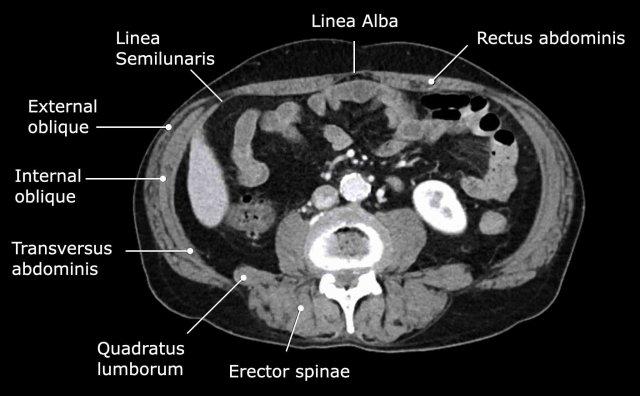

Hệ thống cơ thành bụng

Các cấu trúc cơ quan trọng bao quanh các tạng trong ổ bụng được thể hiện trong hình này.

Đường bán nguyệt (linea semilunaris) là một đường gân cong nằm ở phía ngoài cơ thẳng bụng ở cả hai bên.

Tại đây, bao cơ thẳng trước và sau kết nối với ba cơ thành bụng bên: cơ chéo ngoài, cơ chéo trong và cơ ngang bụng.